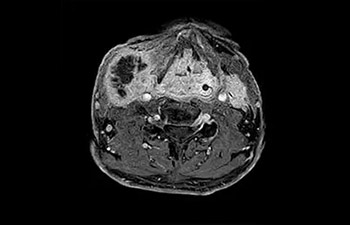

Tobillo

con Compressed SENSE